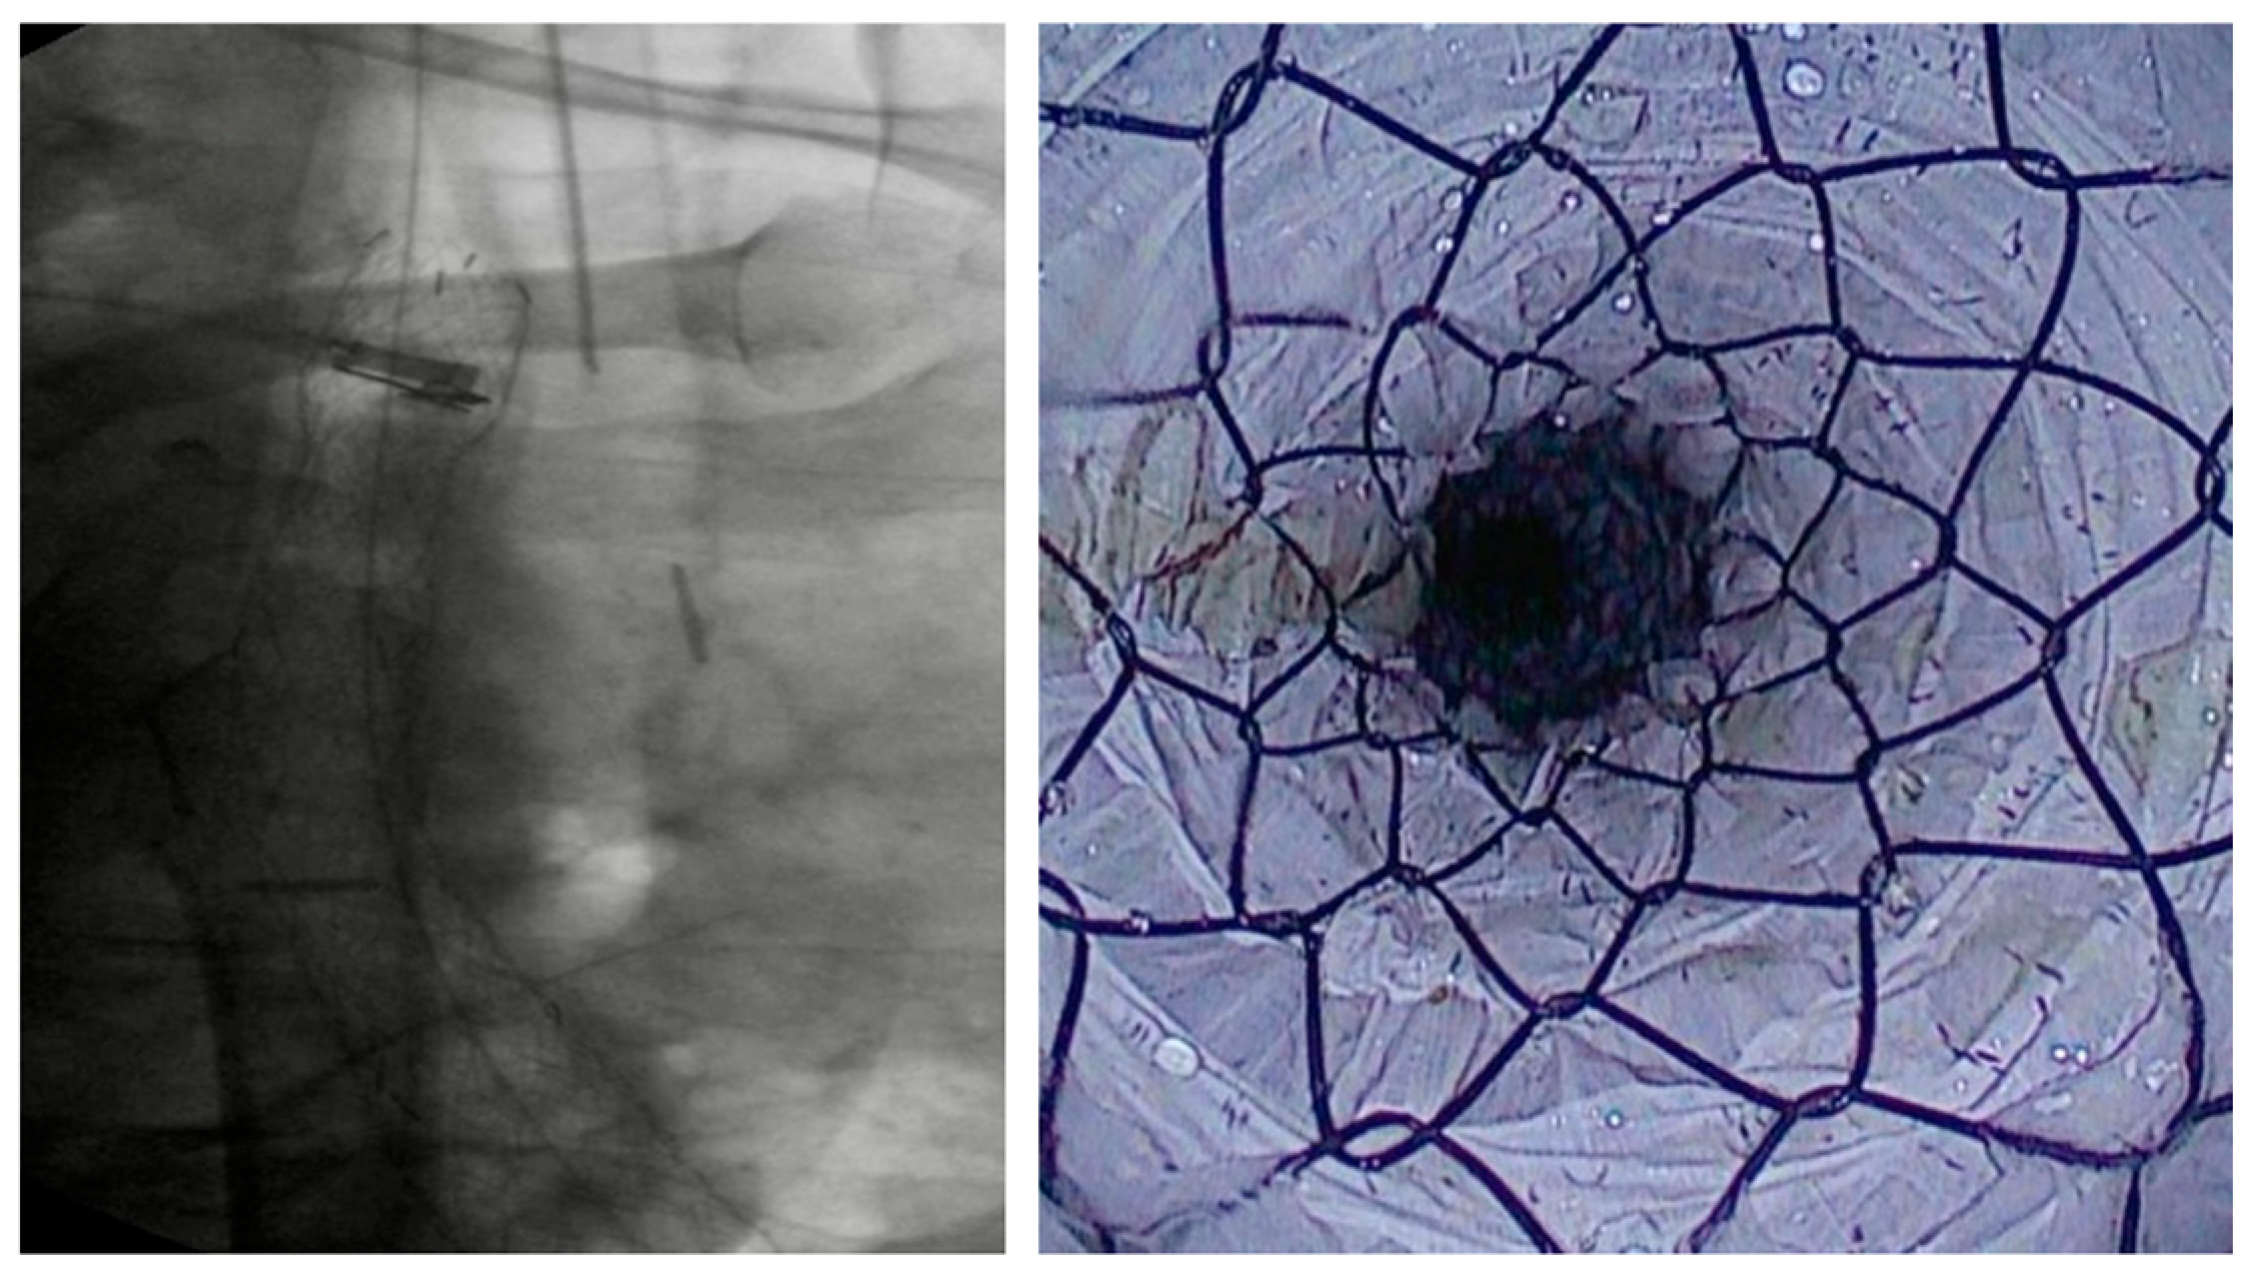

4.1.2. LAMS

Indication and Mechanism of Action

- Direct technique: puncture of the jejunal loop with a 19G needle and contrast injection to confirm position [126].

- Device-assisted EUS-GE: balloon or enteroscope passed across the stenosis to aid EUS visualization and targeting [127].

- Wireless Endoscopic Simplified Technique (WEST): described by Bronswijk et al. in 2020 and currently the most widely used technique [128], this approach involves jejunal distension via a nasoenteric tube with saline and dye, followed by “free-hand” single-step LAMS deployment under EUS guidance [128].